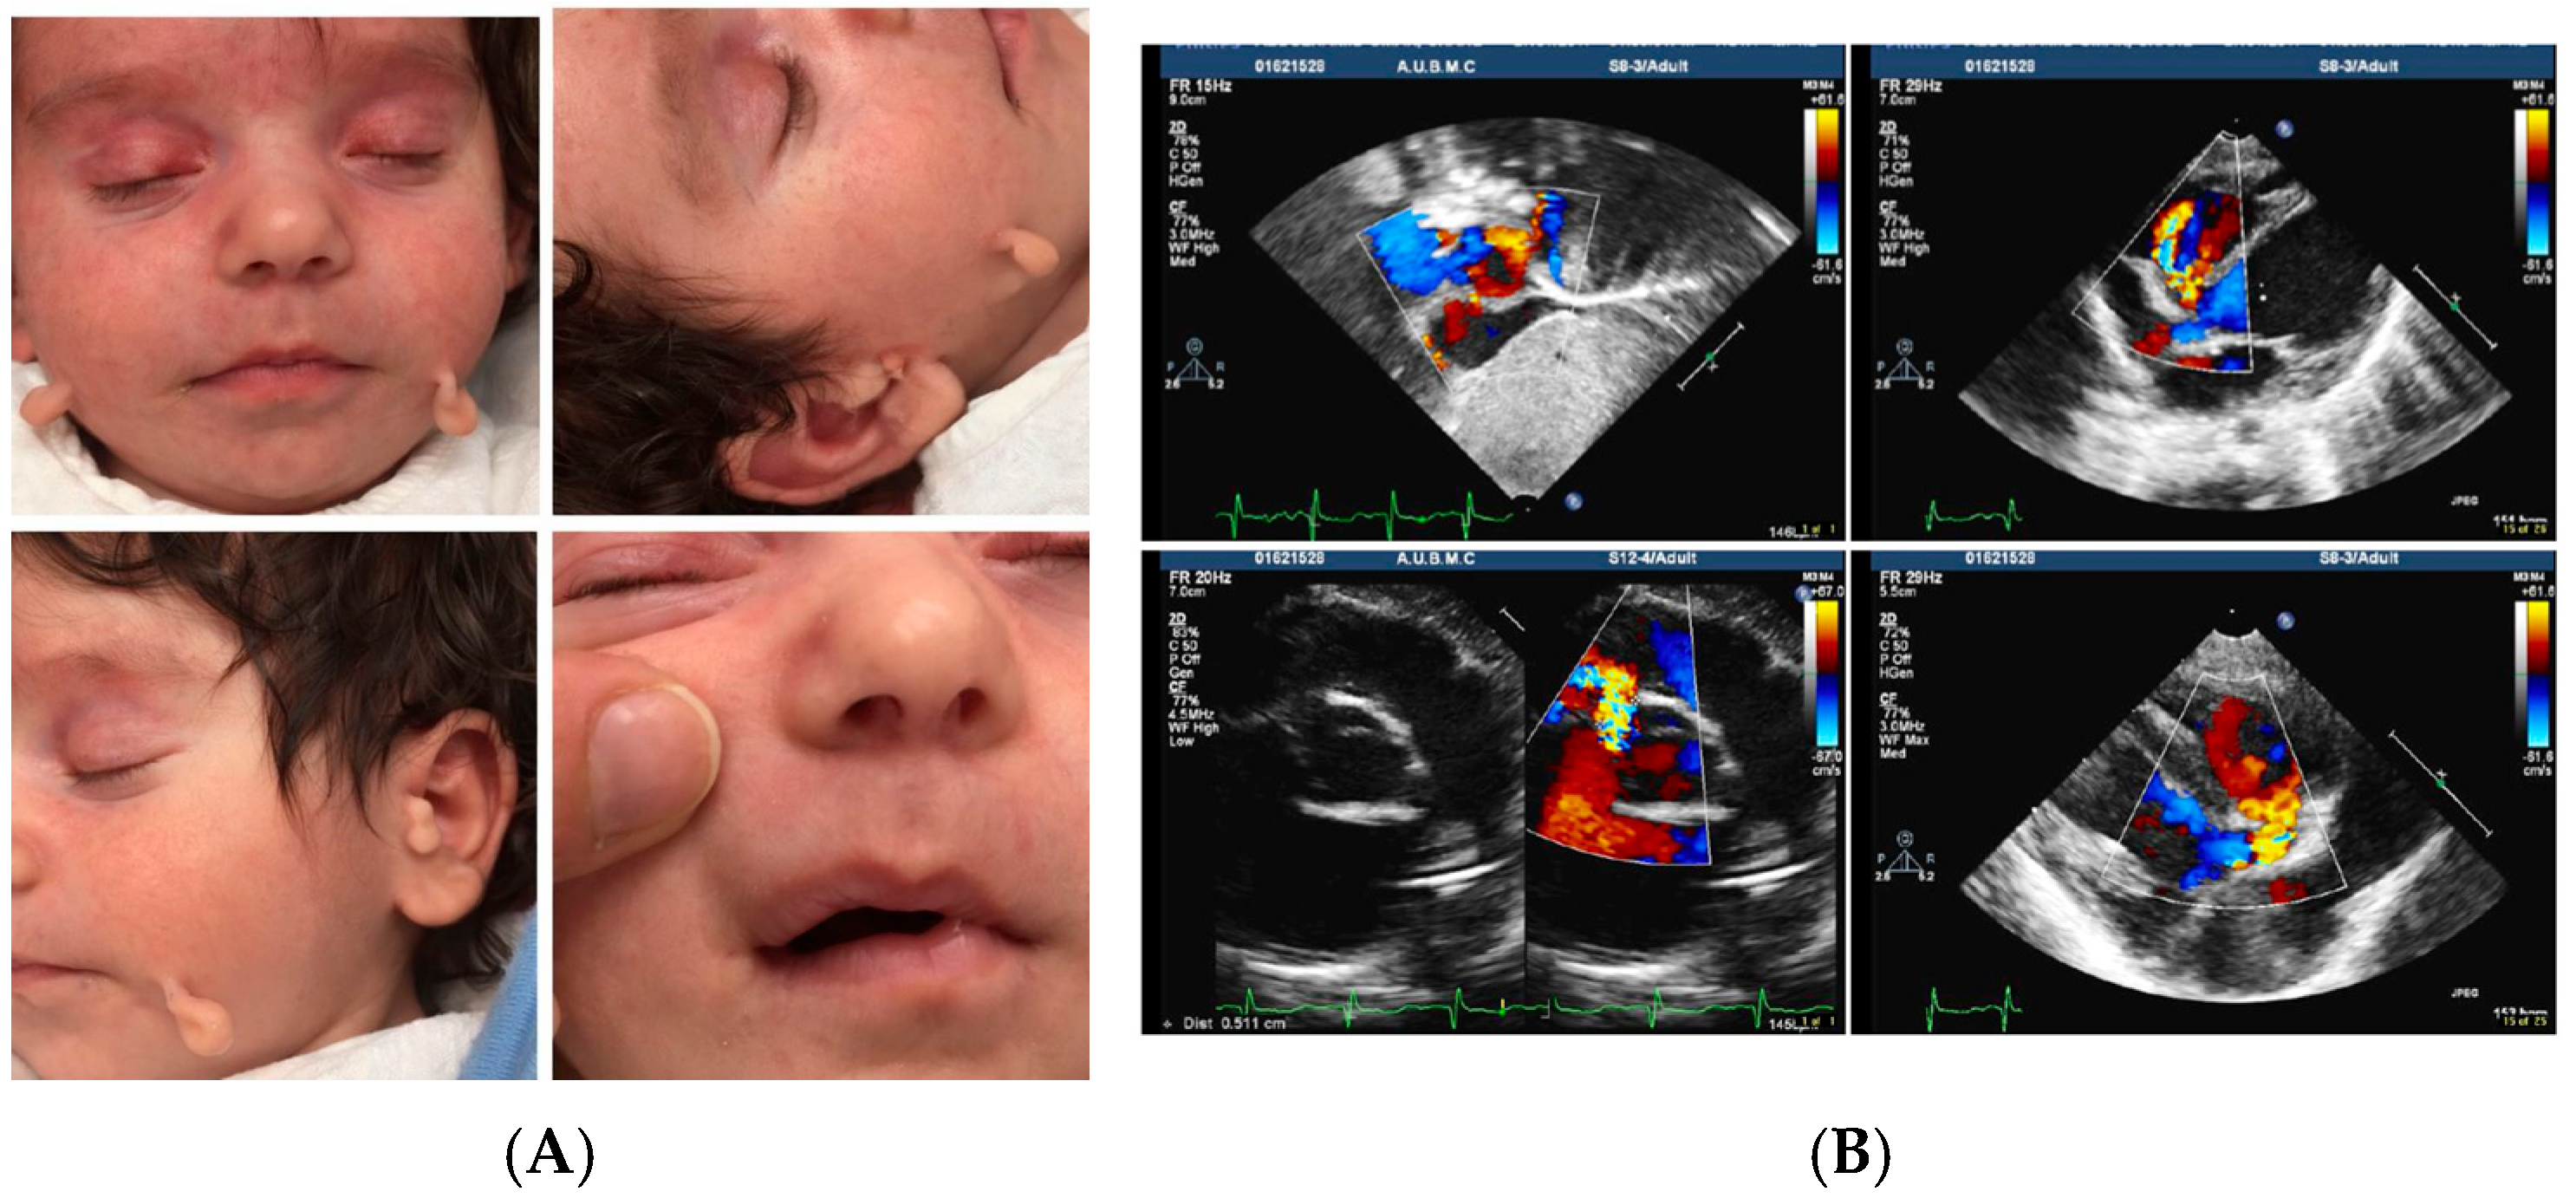

Characterization of a Familial Goldenhar Syndrome Case Using Whole-Exome Sequencing

3. Results